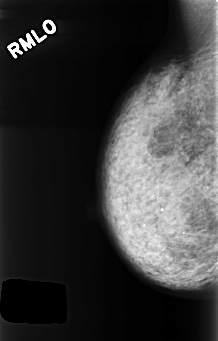

C_0417_1.RIGHT_MLO

RIGHT_MLO LINES 4432 PIXELS_PER_LINE 2824 BITS_PER_PIXEL 12 RESOLUTION 50 NON_OVERLAY

LESION_TYPE MASS SHAPE ASYMMETRIC_BREAST_TISSUE MARGINS ILL_DEFINED

ASSESSMENT 4

SUBTLETY 5

PATHOLOGY BENIGN